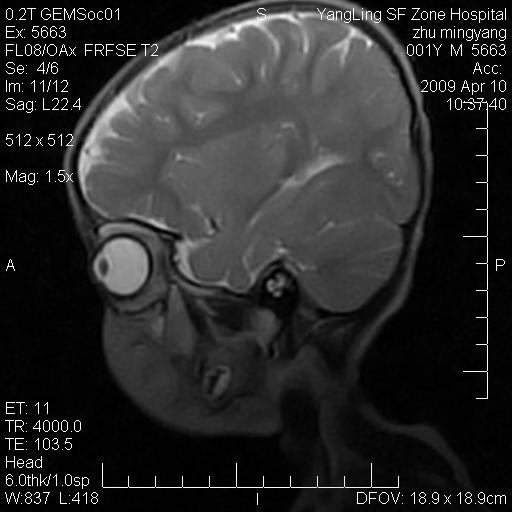

患者:1岁半,两天前外伤收住我院,ct检查小脑占位

考虑星形细胞瘤,建议增强

髓母细胞瘤或血管母细胞瘤,增强后可以鉴别;影像资料见 <。鱼博浪老师的《中枢神经系统ct与mr鉴别诊断》 小脑部肿瘤章节。

髓母细胞瘤或血管母细胞瘤!支持!

支持考虑髓母细胞瘤

考虑----髓母细胞瘤可能性大

考虑髓母细胞瘤或室管膜瘤。

支持髓母细胞瘤。

考虑髓母细胞瘤。

考虑髓母细胞瘤或星形细胞瘤

考虑髓母细胞瘤.

考虑髓母细胞瘤可能性大。

小脑肿瘤.考虑髓母细胞瘤可能.

就病灶部位及临床资料首先考虑髓母.